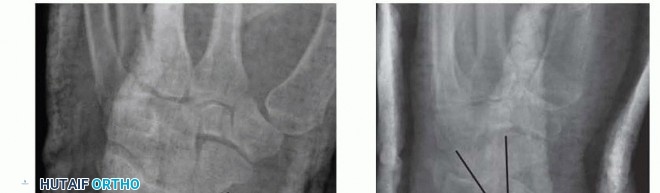

### FIG 2 • A. PA radiograph demonstrating radial inclination

(black lines)

, ulnar variance

(red)

, and radial height

(white bracket)

. B. Lateral radiograph of the wrist demonstrating volar tilt

. Visualize and palpate the hand and fingers for swelling, ecchymosis, tenderness, crepitus, and deformity. Use two-point tool or paper clip bent to 5 mm and touch radial and ulnar aspects of all fingers with one or two points. Greater than normal (5 mm) two-point testing in the form of progressive neurologic deficit may signify an acute or chronic carpal tunnel syndrome.

Posteroanterior (PA), lateral, and oblique radiographic views are critical in evaluating all suspected distal radius fractures. Consider imaging the uninjured wrist for comparison and to serve as a template for surgical reconstruction. Radiographs of the elbow should be obtained in almost all cases, especially if any tenderness, swelling, or deformity is detected clinically. Radiographic measurements taken from the PA view ( FIG 2A) include the following14, 24: Radial inclination, which is the angle between a line perpendicular to the shaft of the radius at the articular margin and a line along the radial articular margin Normal angle: 21 degrees Radial length, which is the distance from a line tangential to the ulnar articular margin to a line drawn perpendicular to the long axis of the radius at the radial styloid tip Normal length 4: 9 to 11 mm Ulnar variance, which is the distance from a line perpendicular to the long axis of the radius at the sigmoid notch and a line tangential to the ulnar articular surface Normal length 4: 0 mm Lateral articular (volar) tilt is the angle between a line for the articular surface of the radius and a perpendicular line to the long axis of the radius. Normal angle: 11 degrees volar tilt ( FIG 2B)4, 14, 24 Computed tomography (CT) scans can fully elucidate the anatomy of the fracture, particularly articular disruption or incongruity. They also help to determine the necessary surgical approach by defining the location and extent of comminution. CT scans increase the interobserver reliability of treatment plans and may actually alter the initial treatment plan based on plain radiographs. 7